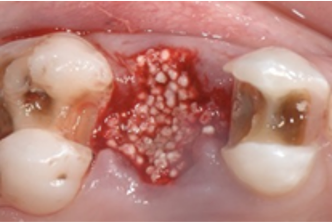

Fig. 2 Ridge preservation with easy-graft CLASSIC, after atraumatic extraction

Fig. 3 Situation at re-entry 4 months post-op. easy-graft CLASSIC granules are well integrated in new bone